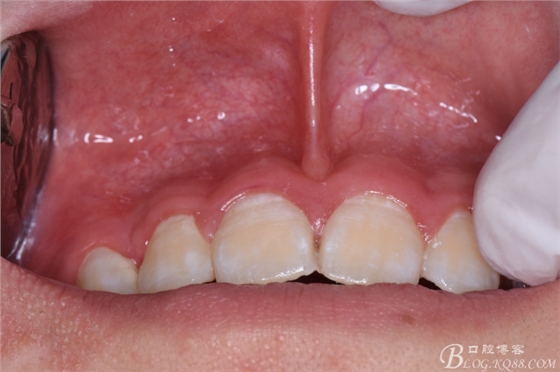

圖1.術(shù)前正畸科的病歷圖片:建議拔除12根方接近鼻底的多生牙及11、21根方倒置多生牙

圖5.唇側(cè)未能捫及明顯隆起,考慮手術(shù)的課操作性及視野清楚,結(jié)合cbct,從唇側(cè)前庭溝處做弧形切口